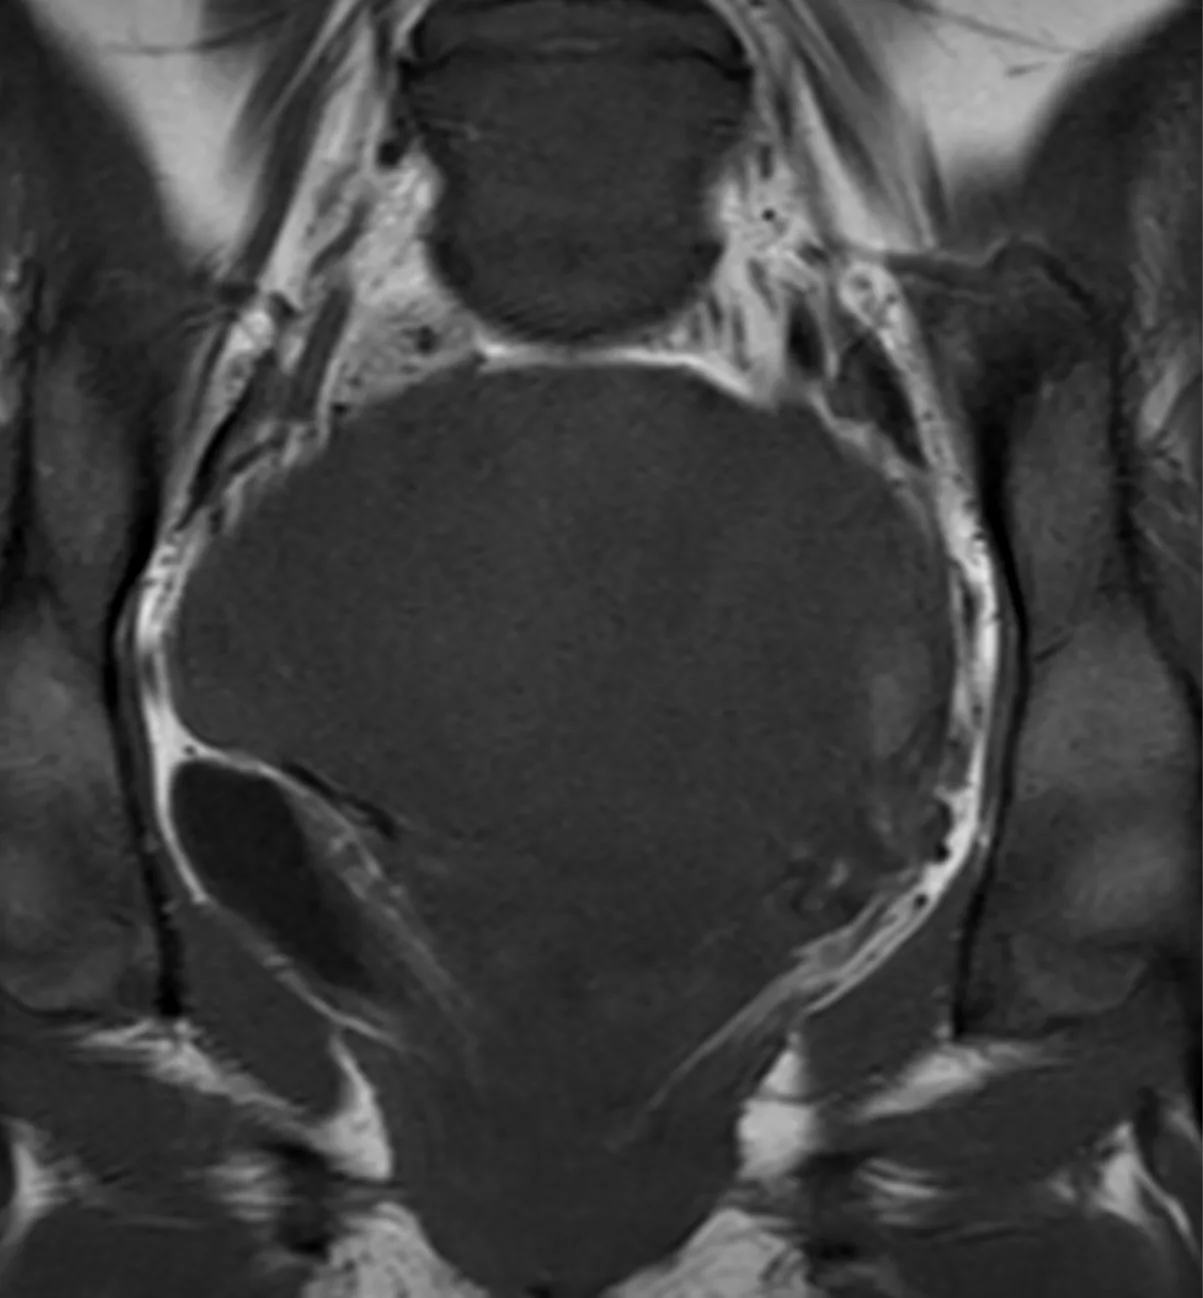

Достаточно курьёзный случай: коллега просит консультации и спрашивает: Андрей Эльдарович, посмотрите, это перегородчатая матка? А снимки вот такие. При внимательной оценке можно, во-первых, понять, что это просто артефакт "удволения" контура (ghosting) из-за движений в передне-заднем направлении, скорее всего, из-за дыхательных экскурсий, во время сканирования, тем паче, что сагиттальный скан есть переделанный и "нешевеленный". А во-вторых, хороший повод вспомнить, что в процессе органогенеза матка формируется из двух половин, правой и левой, и перегородка в ней, если и имеется, то может быть лишь в сагиттальной, а никак не во фронтальной, плоскости. Будьте внимательны и осторожны, как говорится. 😎💀